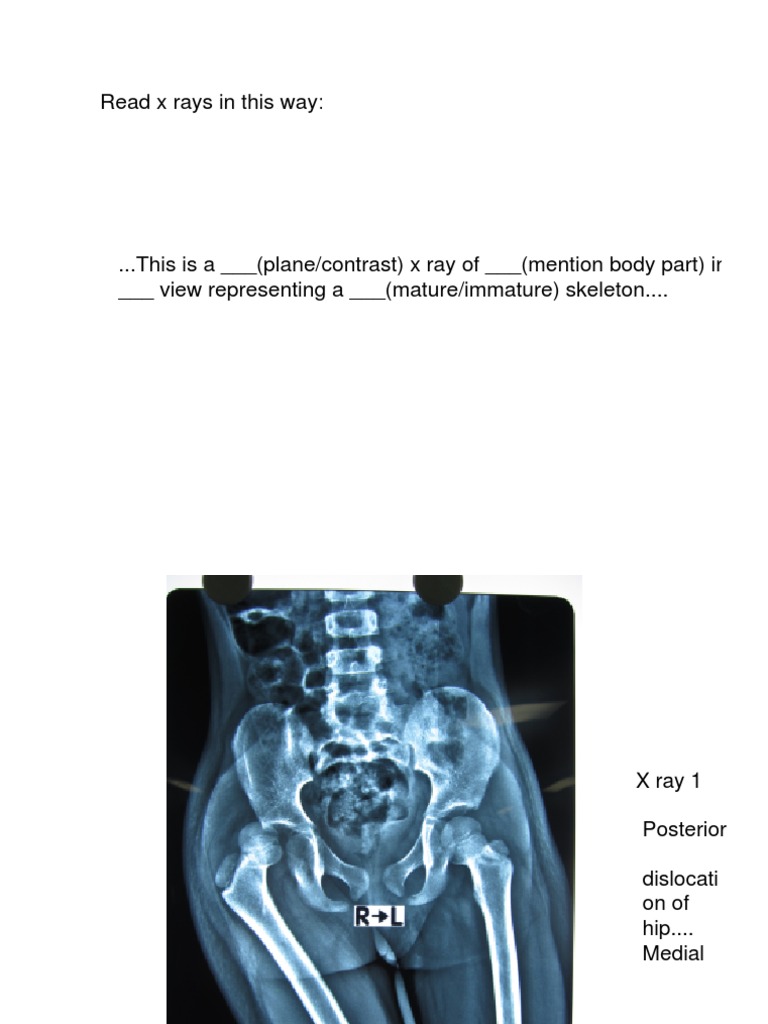

Ortho Dx A woman with a hip that is popping out of place Clinical Ortho X Ray Views Check for any signs of fractures, this can usually be done. Demonstrate the joint space, yet sacrifices any assessment of fluid levels. Lateral/scapula y view (named due to the “y” shape of the scapula in this view) an. orthogonal view of the ap projection. Gravity stress = supine + hip er +. Provides better detail of cortical and trabecular. Ortho X Ray Views.